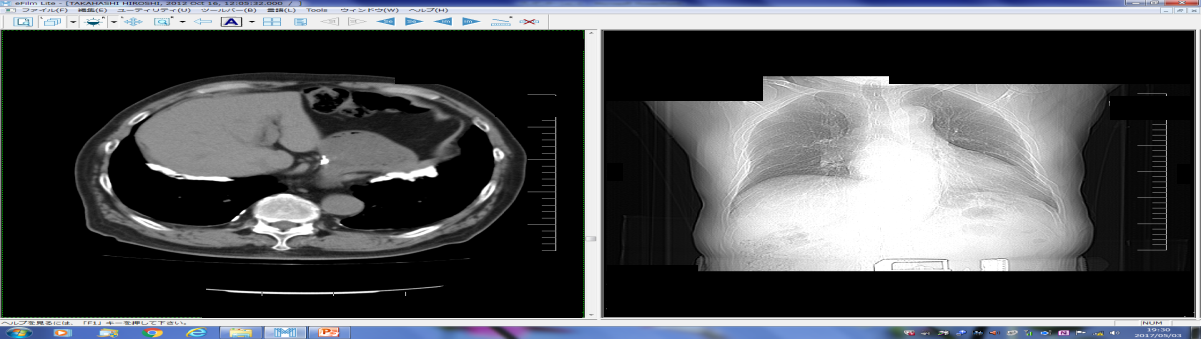

70歳男性、A医大で悪性胸膜中皮腫上皮型T1a.N0と診断された。職業歴は1949-1950年農業、1950-1966年製紙用金網製造会社織工、1966-1969年喫茶店経営。1969年-2003年私鉄駅高架下文具店店長。2階倉庫の吹き付け材には、クロシドライトが25%含。解剖肺内アスベスト繊維濃度19.0×106本/乾燥1g解剖のアスベスト繊維でクロシドライト11本、クリソタイル・アモサイト1本合計13本観察した11)【図5】【写真5】。

• 2階倉庫の吹付け材にはクロシドライトが25%

• 文具店2階の静穏時の濃度は1.13~4.2f/L

• 1階に荷物搬入時の濃度は14.0f/L

• 2階に荷物搬入時と清掃時の濃度は136.5f/L

• 文具店1階は0.34~1.13f/L

• 文具店外の大気中の濃度は定量下限値